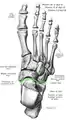

Vue du dessus du pied selon Sobotta, avec l'articulation de Chopard dessinée d'une ligne verte.